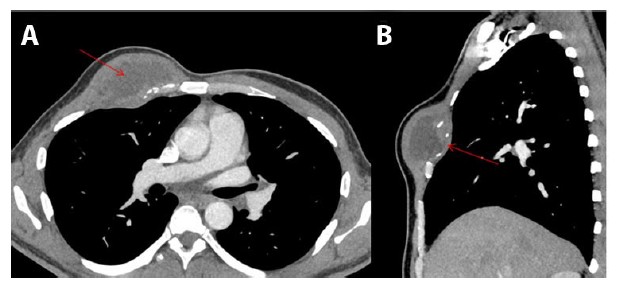

The facial symptoms worsened over a span of next two days for which he presented to the emergency department with the non-healing facial wound and cellulitis accompanied by fever and myalgia. Computed tomography (CT) scan revealed an anterior inferior right facial cellulitis along with bilateral cervical lymphadenopathy (images not shown). Wound cultures were performed which came back positive for Coccidioides (serum antibody titers of 1:4096). The patient was treated with Bactrim and Fluconazole; the latter was given for about five months; however, the symptoms did not improve. Subsequently, he complained of a fluctuating lesion in his right leg, accompanied by hip pain. Computed tomography scan revealed a small abscess with a communication to the skin within the subcutaneous fat of the right lateral thigh, bony erosion of the left parasymphyseal pubic body, right greater trochanter, and enlarged right pelvic sidewall low density necrotic lymph nodes. With the ongoing symptomatology and refractoriness to Fluconazole, Posaconazole was added to the antifungal regime. Subsequently, the patient developed anterior right chest wall complex collection measuring 6.4 cm and involving the right pectoralis muscle with extension into the third anterior intercostal extra pleural space (Figure 1A and Figure 1B). Despite the ongoing antibiotic treatment and supportive measures, the infection spread to the parietal pleura. History of significant weight loss (about 50 lb) within a span of few months was present as well. Additionally, patient’s blood glucose levels were variable and ranged from 113 to 353 mg/dl during the course.

Figure 1: Axial (A) and sagittal (B) CT scan images demonstrate expansile lytic lesion (red arrows) involving right anterior rib with associated soft tissue collection which extends into the subcutaneous tissue with a small extra pleural component.